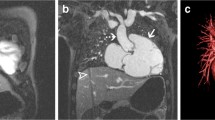

A representative example is shown in Fig. 3, which highlights improved delineation of the ventricular septum. Further, Fig. 4 shows the same patient but at a more superior slice level showing delineation of the coronary arteries in the atrio-ventricular grooves. Figure 5 shows a representative image from another child highlighting improved delineation of the aortic root, main pulmonary artery and a central catheter. Further, Fig. 6 highlights similar delineation of extra-cardiac structures. Finally, Fig. 7 shows an example of the technique compared with a suspended respiration acquisition.

Same child as Fig. 3. With triggering, coronary arteries can be seen (arrows)

Another 3-year-old boy with repaired tetralogy. Top: Source coronal images. Note diminished cardiac ghosting artifacts (white arrow), improved delineation of right coronary artery (curved arrow), and right ventricular trabeculations (solid black arrow). Bottom: Sagittal reformats with triggered images show left anterior descending coronary (white arrow), left circumflex coronary artery (curved black arrow) and left pulmonary veins (solid white arrows)